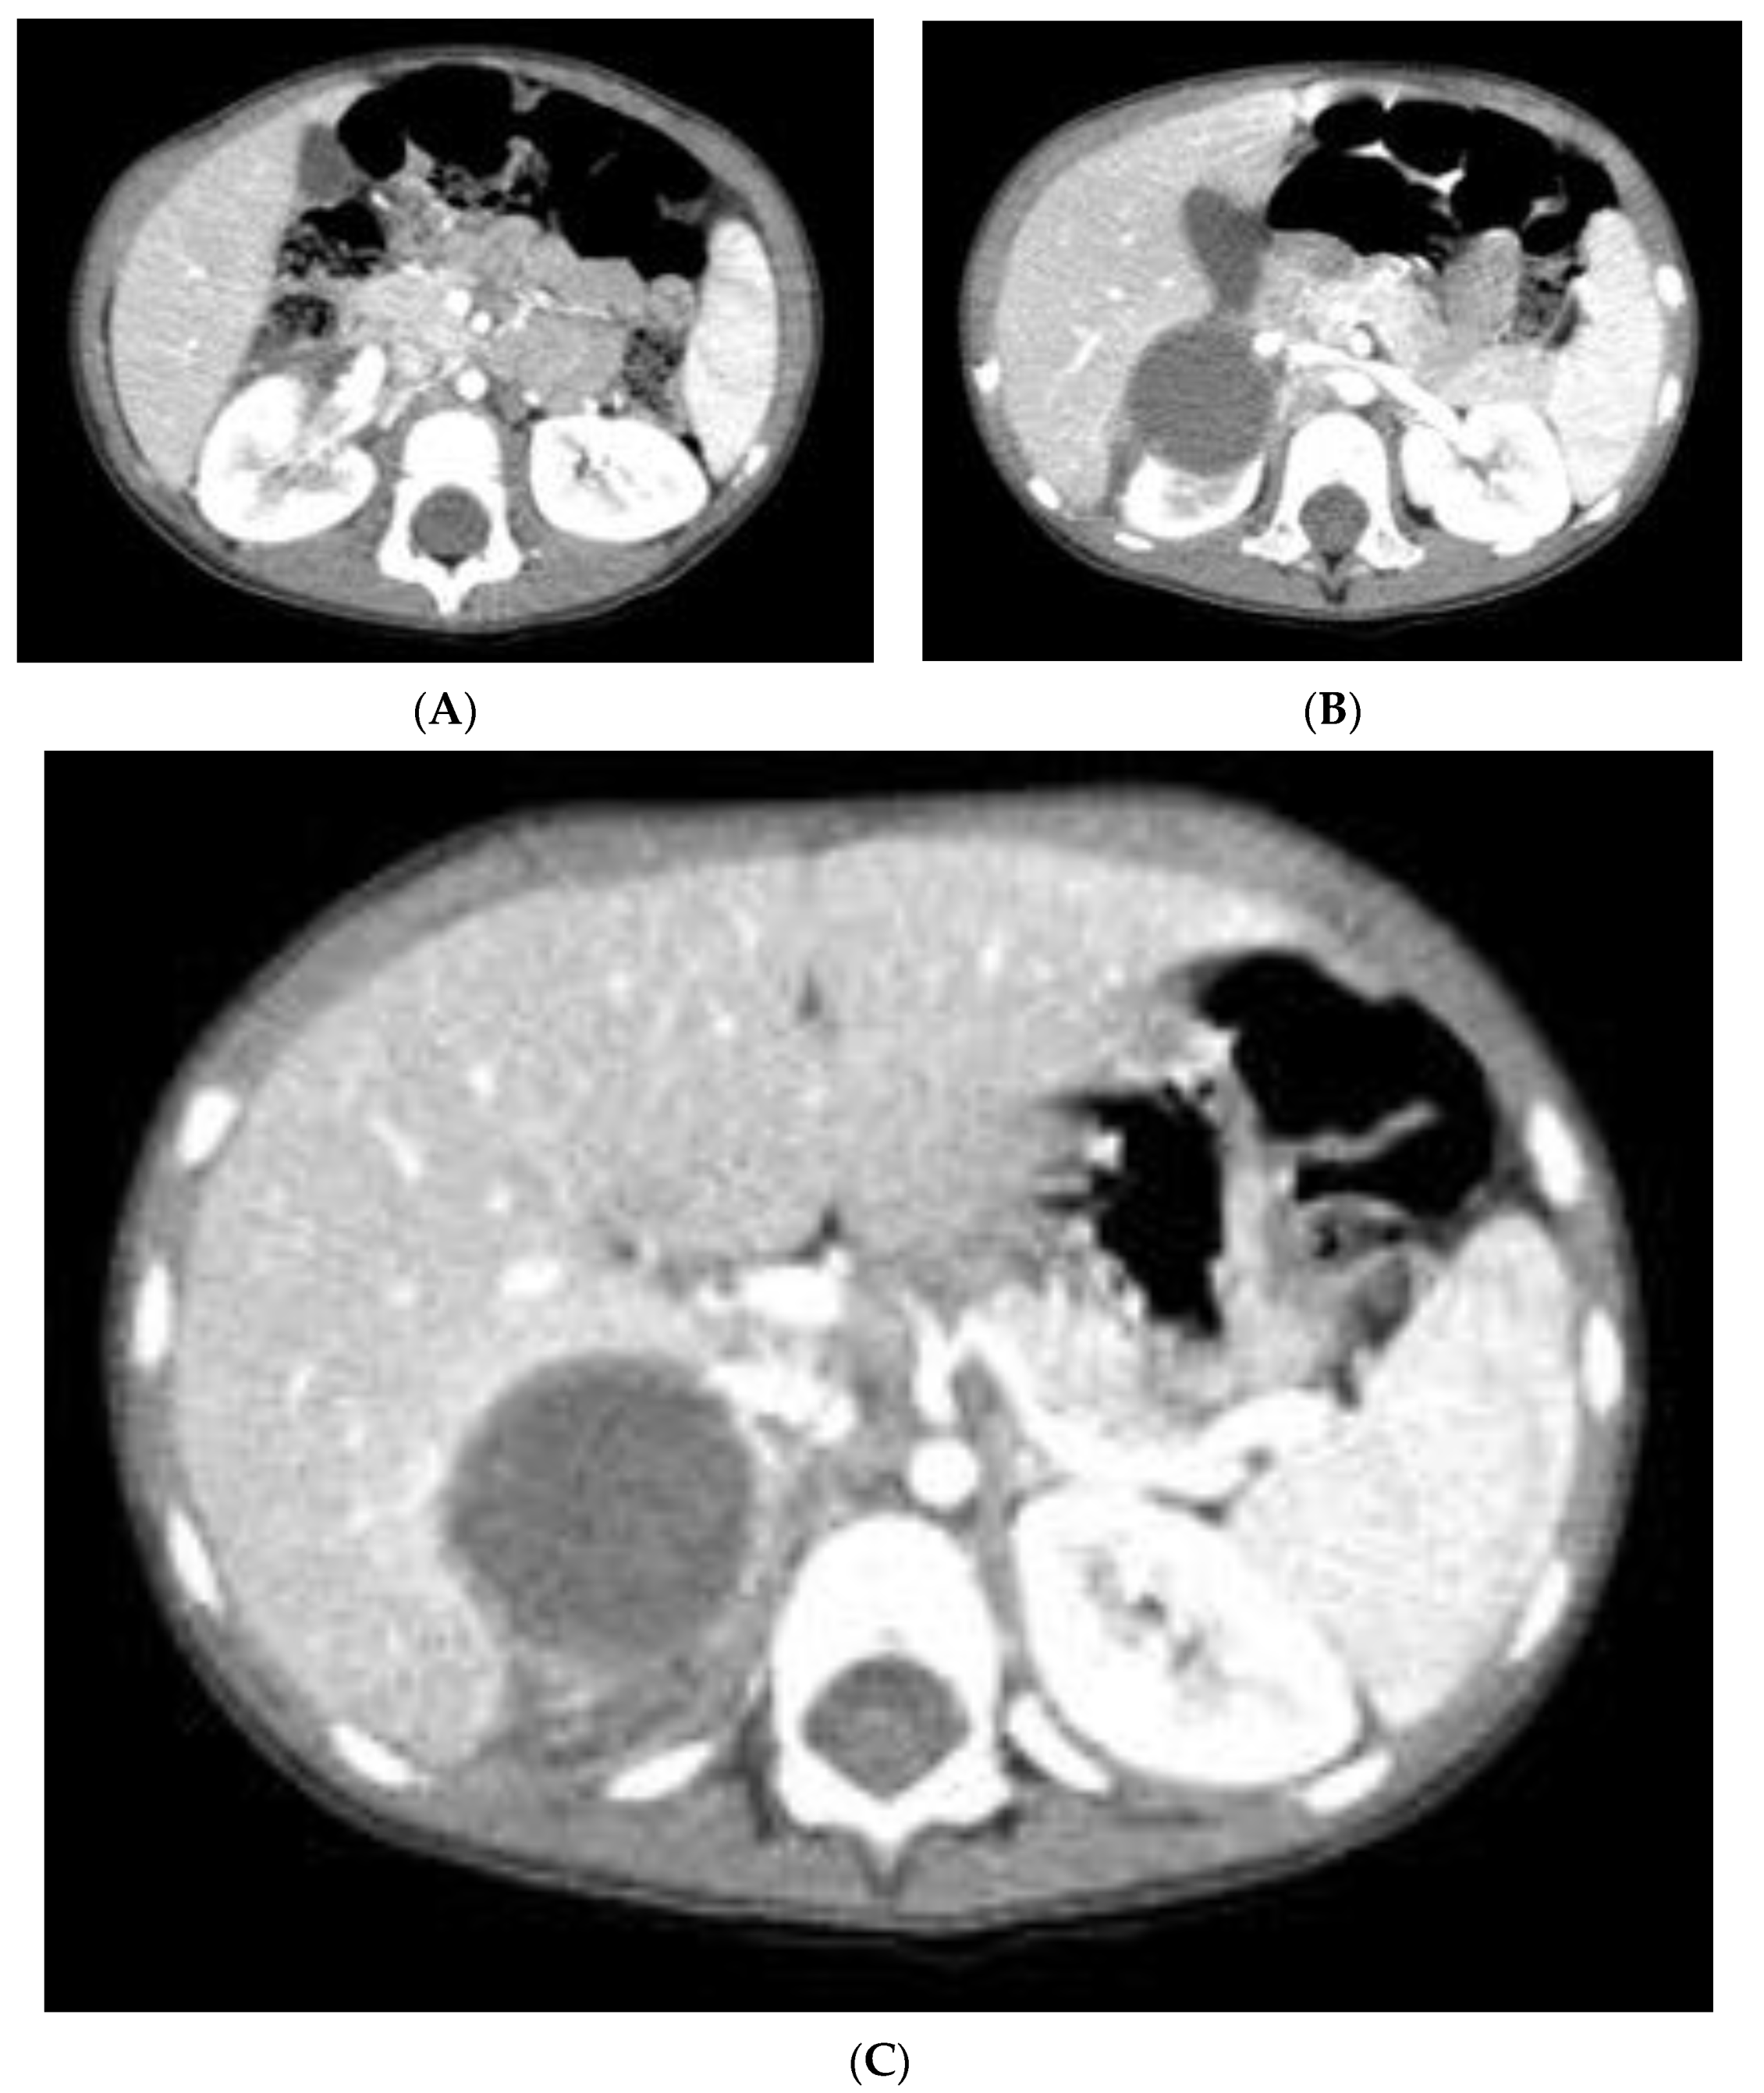

2. Case Report